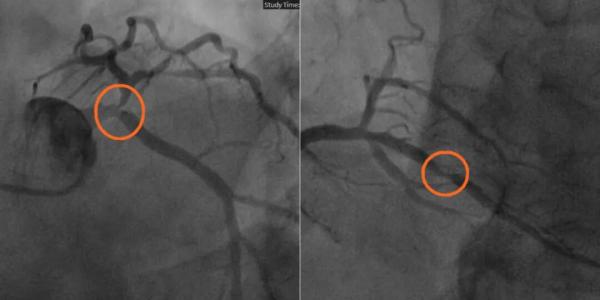

他的冠脉造影结果,让所有人捏了一把汗:左主干狭窄90%、左前降支狭窄99%、右冠脉狭窄95%,给供血心脏的道路几乎全线堵死!这种多支严重病变,随时可能让心脏的泵血功能衰竭,导致全身血液供应瘫痪,患者生命将危在旦夕。

▲造影影像